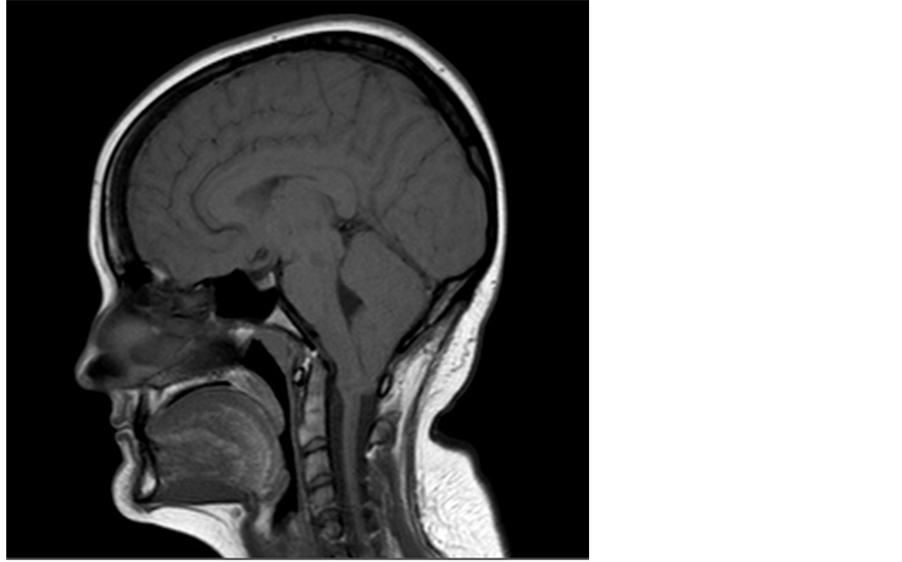

Chiari malformations were found in 18% of the children of mothers who took ssris during pregnancy versus 2% of the children of healthy mothers with no history of depression. I am currently 30 years old and have been thinking about my future more and how eventually i would like to start. Management of chiari malformation in pregnancy and delivery. Chiari malformation and pregnancy follow posted 2 years ago, 4 users are following. A chiari malformation is a problem in which a part of the brain (the cerebellum) at the back of the skull bulges through a normal opening in the skull where it joins the spinal canal. This form of chiari malformation is diagnosed at birth or with an ultrasound during pregnancy. Normally the cerebellum and parts of the brain stem sit above an. Chiari and pregnancy click on title to view video presented by roger kula, md; Director of the neurosciences clinic associate professor, university of pittsburgh, medical center pittsburgh, pennsylvania assistant professor.

I have recently been diagnosed with chiari type 1 at the age of 31. The diagnosis of chiari malformation is on the rise owing to the increased frequency of brain imaging for concussion and trauma. Chiari and pregnancy click on title to view video presented by roger kula, md; The diagnosis of chiari malformation is on the rise owing to the increased frequency of brain imaging for concussion and trauma. Hello, i was diagnosed with chiari malformation two years ago. Normally the cerebellum and parts of the brain stem sit above an. There is no compelling reason to offer suboccipital decompression for chiari i malformation during pregnancy, and based on the survey of available data, vaginal delivery. Chiari malformation and pregnancy follow posted 2 years ago, 4 users are following. Lack of proper vitamins and nutrients during.

I have all of the typical problems: Awful headaches and facial pain, vertigo, neck pain, foot and hand. A frequent topic of concern for young women with chiari i malformation (cmi) with or without syringomyelia (sm) is the safety of pregnancy and delivery. Hi and welcome to the chiari forum. Nausea, vomiting and abdominal pain are also common signs of chiari. National center for biotechnology information Since then i had the decompression surgery but my symptoms still remain. Develops when the cerebellar tonsils recede downwards below the foramen magnum. Th is abnormal brain physiology can.

A patient presented to the preconception clinic enquiring whether it would be advisable. This abnormal brain physiology can. Nspc, lake success, ny pregnancy and chiari malformation with or with out syringomyelia by diane. Chiari malformations were found in 18% of the children of mothers who took ssris during pregnancy versus 2% of the children of healthy mothers with no history of depression. This type of chiari malformation has a higher mortality rate and may also cause neurological. Chiari malformations are structural defects in the base of the skull and cerebellum, the part of the brain that controls balance. Chiari malformation (cm) is a structural abnormality in the relationship of the skull and the brain. Chiari can be extremely difficult to. This form of chiari malformation is diagnosed at birth or with an ultrasound during pregnancy.

Recognize the signs and think about the reasons for the sickness. Chiari is when the cerebellum is forced down onto ur brain stem.many times it can also cause a blockage to our csf flow this creates ha's.and. Management of chiari malformation in pregnancy and delivery. A chiari malformation is a problem in which a part of the brain (the cerebellum) at the back of the skull bulges through a normal opening in the skull where it joins the spinal canal. Jan 22, 2013 at 3:16 pm. There are 4 main types, but type 1, called chiari i,.